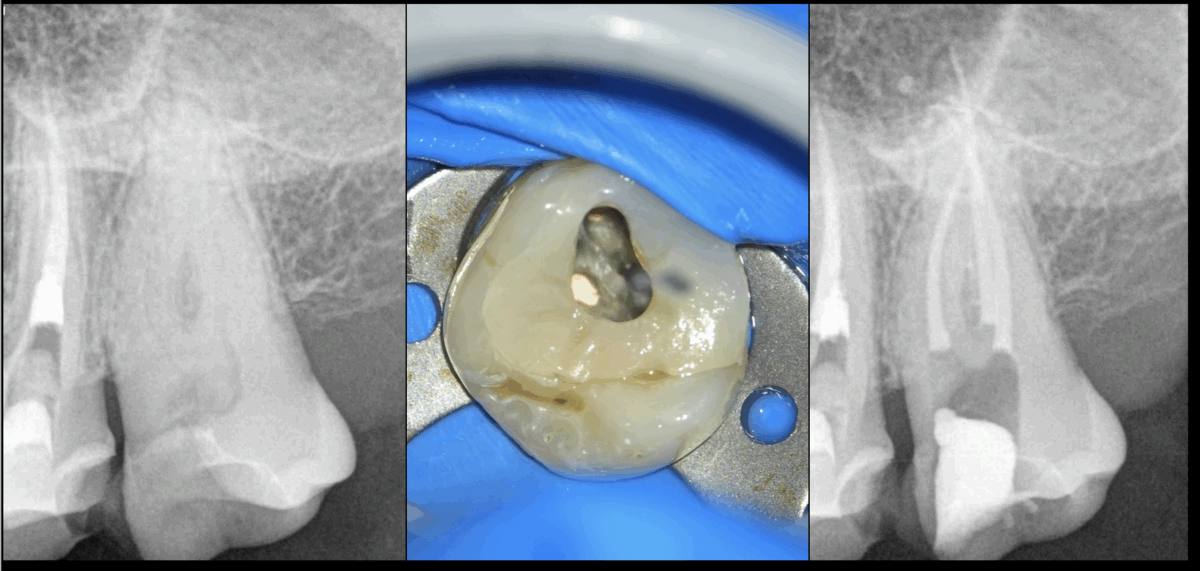

🦷 Traitement initial de la 27 !

Simple ? Basique ?

🤔 𝐏𝐚𝐬 𝐪𝐮𝐚𝐧𝐝 𝐥𝐚 𝐥𝐢𝐦𝐢𝐭𝐚𝐭𝐢𝐨𝐧 𝐝’𝐨𝐮𝐯𝐞𝐫𝐭𝐮𝐫𝐞 𝐛𝐮𝐜𝐜𝐚𝐥𝐞 𝐞𝐬𝐭 𝐚̀ 𝟏 𝐝𝐨𝐢𝐠𝐭 !

➡️ Ce qui qualifie ce cas de « très difficile » d’après les guidelines d’évaluation des difficultés par l’AAE (Association Américaine des Endodontistes).

📌 𝐋𝐞𝐬 𝐚𝐮𝐭𝐫𝐞𝐬 𝐜𝐫𝐢𝐭𝐞̀𝐫𝐞𝐬 𝐚̀ 𝐩𝐫𝐞𝐧𝐝𝐫𝐞 𝐞𝐧 𝐜𝐨𝐦𝐩𝐭𝐞 𝐩𝐨𝐮𝐫 𝐞́𝐯𝐚𝐥𝐮𝐞𝐫 𝐥𝐚 𝐝𝐢𝐟𝐟𝐢𝐜𝐮𝐥𝐭𝐞́ :

• L’historique médical

• Les ATCD de problèmes anesthésiques

• Le niveau de coopération du patient

• Le réflexe nauséeux

• Le niveau de situation de l’urgence

• La difficulté diagnostique, la difficulté à prendre des radios

• La position de la dent sur l’arcade (type de dent, inclinaison, rotation…)

• La difficulté d’isolation

• La morphologie canalaire et radiculaire…

🪑 𝐄𝐧 𝐫𝐞́𝐬𝐮𝐦𝐞́ : 𝐜̧𝐚 𝐩𝐞𝐮𝐭 𝐬𝐞𝐦𝐛𝐥𝐞𝐫 𝐬𝐢𝐦𝐩𝐥𝐞 𝐬𝐮𝐫 𝐮𝐧𝐞 𝐫𝐚𝐝𝐢𝐨 𝐞𝐭 𝐞̂𝐭𝐫𝐞 𝐭𝐞𝐫𝐫𝐢𝐛𝐥𝐞𝐦𝐞𝐧𝐭 𝐝𝐢𝐟𝐟𝐢𝐜𝐢𝐥𝐞 𝐬𝐮𝐫 𝐥𝐞 𝐟𝐚𝐮𝐭𝐞𝐮𝐢𝐥 ! 😉